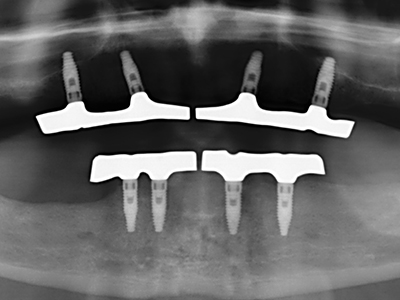

En la extracción de bloques óseos la piezocirugía también presenta ventajas adicionales: Además de la alta precisión en la osteotomía que ya se ha descrito antes, se ha comprobado que el uso de los delgados insertos de sierra resulta especialmente cuidadosas con el hueso. Frente a esto, sobre todo cuando se usan las fresas de Lindemann, cabe esperar pérdidas en la extracción significativamente más altas debido al mayor grosor de la parte frontal del cabezal (Lakshmiganthan, Gokulanathan et al. 2012). La separación basal que se necesita en particular en los injertos de bloque extraídos de forma retromolar se ve facilitada mediante sierras perpendiculares especialmente previstas a tal fin, lo que permite considerar que la cirugía piezoeléctrica es un procedimiento preciso y seguro para la obtención de bloques de hueso en el área retromolar (Happe 2007) (fig. 1-12).

Como ya se ha demostrado en el pasado, básicamente cualquier procedimiento de cirugía de hueso representa una posible indicación para la cirugía piezoeléctrica. Así, la preparación del segmento móvil en la osteogénesis de distracción (fig. 23-25) y en la osteotomía de sándwich puede realizarse con piezas especiales, sin poner en peligro el suministro sanguíneo de la parte crestal, que resulta esencial para el éxito de ambas técnicas (González-García, Diniz-Freitas et al. 2008).